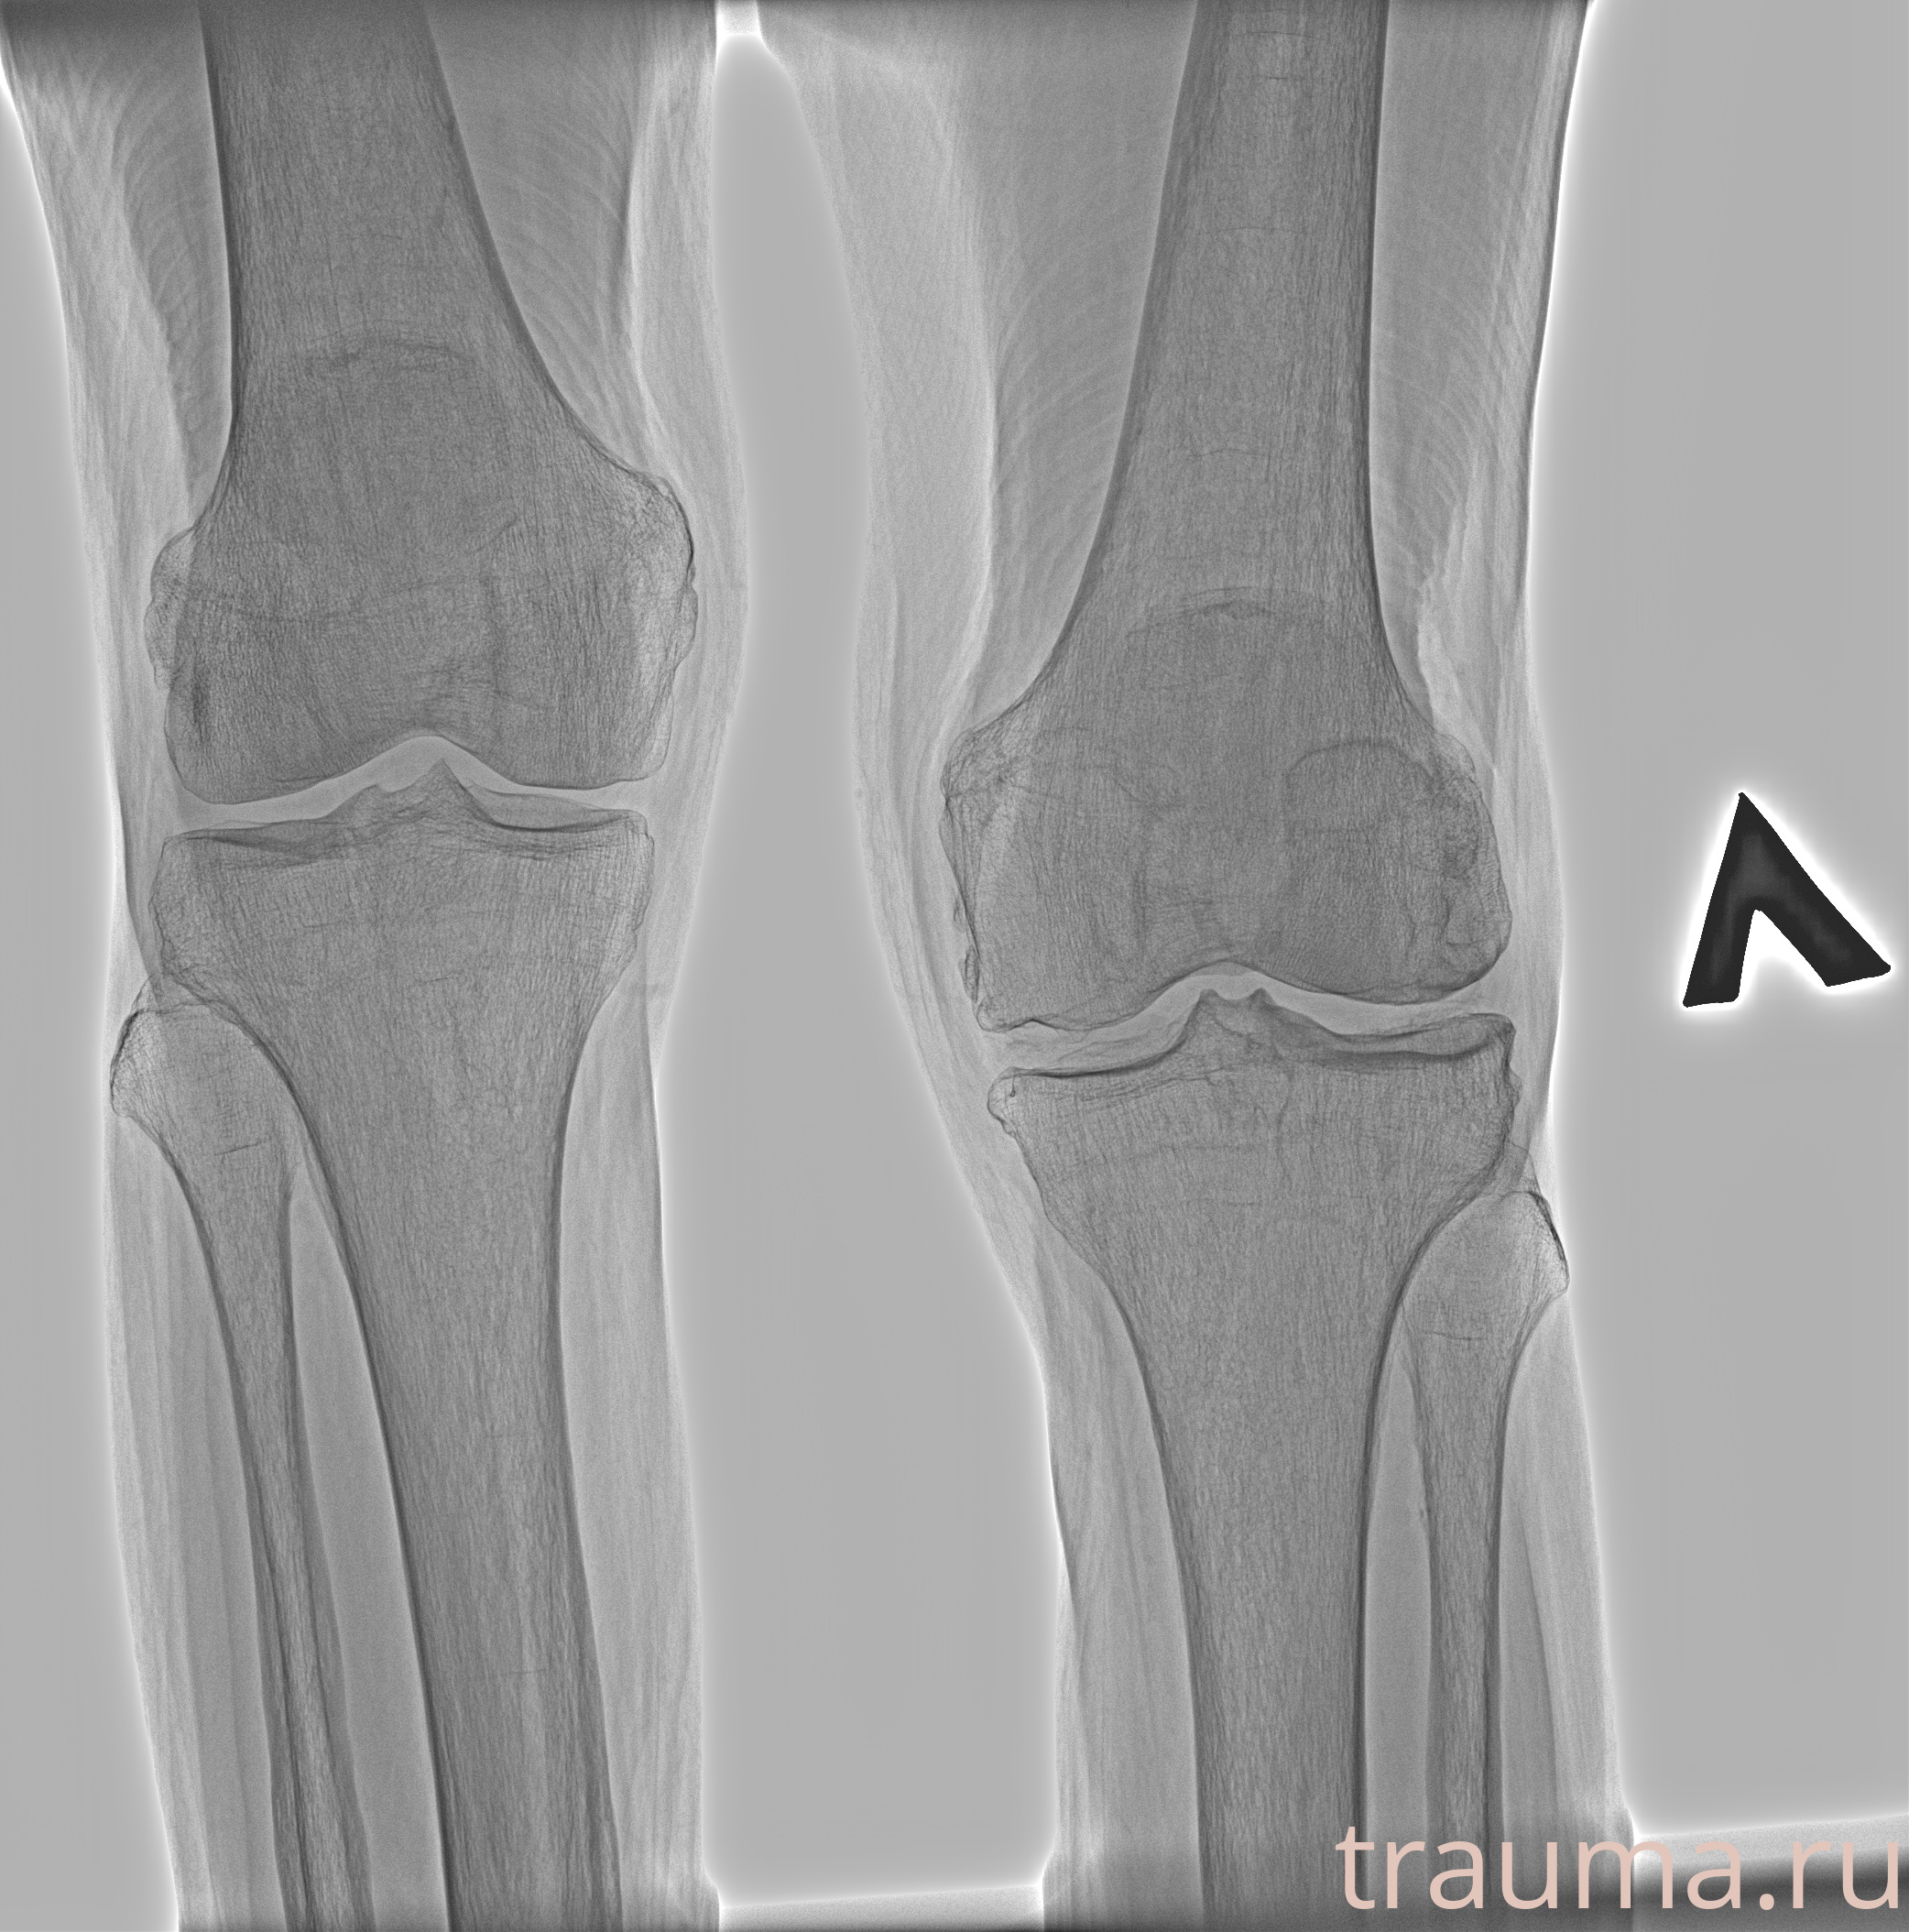

Рентген на дому: по вашему адресу приезжает врач-рентгенолог, травматолог-ортопед с мобильным рентгеновским аппаратом, проводит диагностику травмы или заболевания, делает необходимые рентгенограммы, дает рекомендации по дальнейшему лечению. Получить качественные снимки в домашних условиях возможно благодаря уникальной методике, разработанной МосРентген Центром для института  Склифосовского